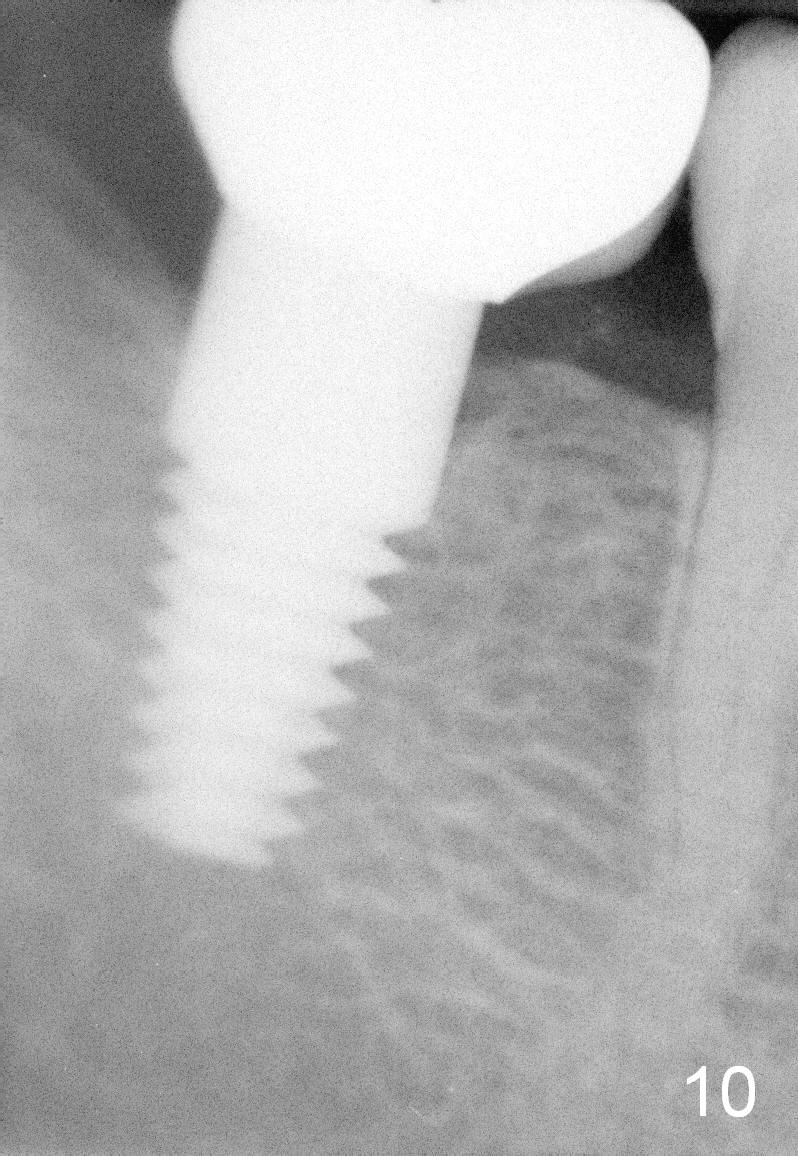

The mesial lamina dura disappears 12 months post cementation or 18 months postop (Fig.10).